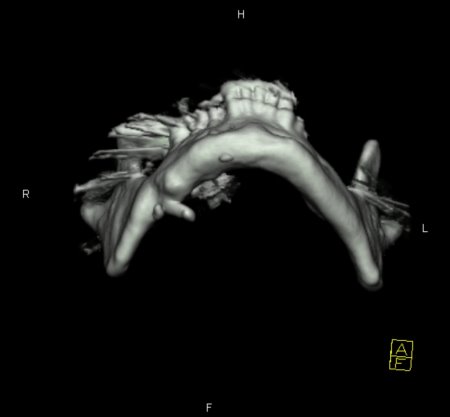

Zur genauen Planung der Kieferkorrektur wurde ich zum CT geschickt. Aus den scheibchenweisen Bildern setzte der Computer ein dreidimensionales Bild zusammen. Dabei ist auch sehr deutlich dieses verlagerte Knochenstück zu sehen.

Zwischenzeitlich stand auch mal die Überlegung im Raum, eine Kinnplastik durchzuführen, bei der die Kinnspitze abgesägt und danach im "richtigen" Winkel wieder aufgesetzt wird. Das klang natürlich auch erst mal ein bissel erschreckend - aber schließlich zählt das Ergebnis. Nach Auswertung der 3-D-Annimation wurde dann allerdings "nur" die erstbeschriebene Kieferkorrektur durchgeführt.